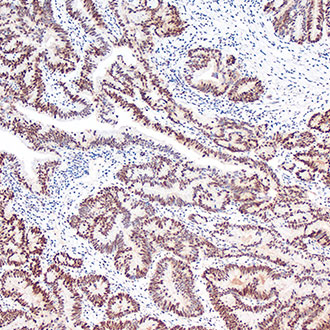

PMS2

PMS2 -